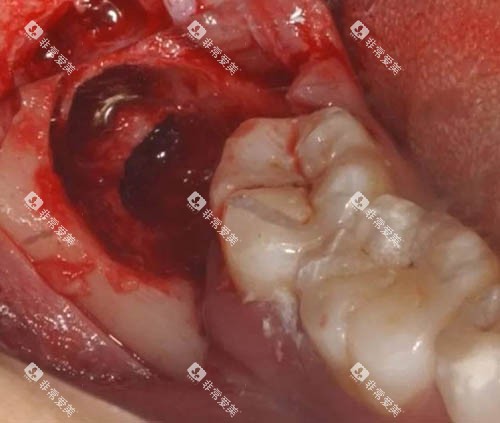

我闺蜜的阻生智齿就是在这里拔的,埋伏得比较深,本来很担心。医生先拍了详细的片子,耐心分析了几种方案,然后选择了更稳妥的一种。整个过程比想象中顺利,医生操作时很专注,护士也一直在旁边安抚情绪。术后还提供了免费复查服务,复查时会仔细检查伤口愈合情况,还会教正确的刷牙方式。